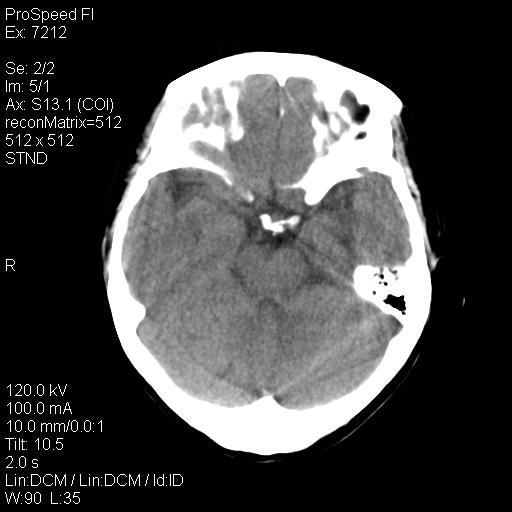

标题: CT18636:F 44Y,头痛三个月,左侧肢体麻木一周。临床诊断, [打印本页]

右额叶脑沟变浅,脑表面见新月形稍高密度影,考虑慢性硬膜下出血可能。

左侧额颞部慢性英模下血肿。

1)考虑左侧额部慢性硬膜下血肿(或硬膜下积液)。2)颅骨骨髓瘤不排除;建议行进一步检查。

1)考虑左侧额颞部及右侧额部慢性硬膜下血肿(或硬膜下积液)。2)颅骨骨髓瘤不排除;建议行进一步检查。

1)右侧半卵圆中心腔隙性脑梗塞。2)考虑左侧额部慢性硬膜下血肿(或硬膜下积液)。3)颅骨骨髓瘤不排除;建议行进一步检查。

慢性硬膜下积液,颅骨改变建议结合本周氏蛋白及其他检查除外骨髓瘤 。